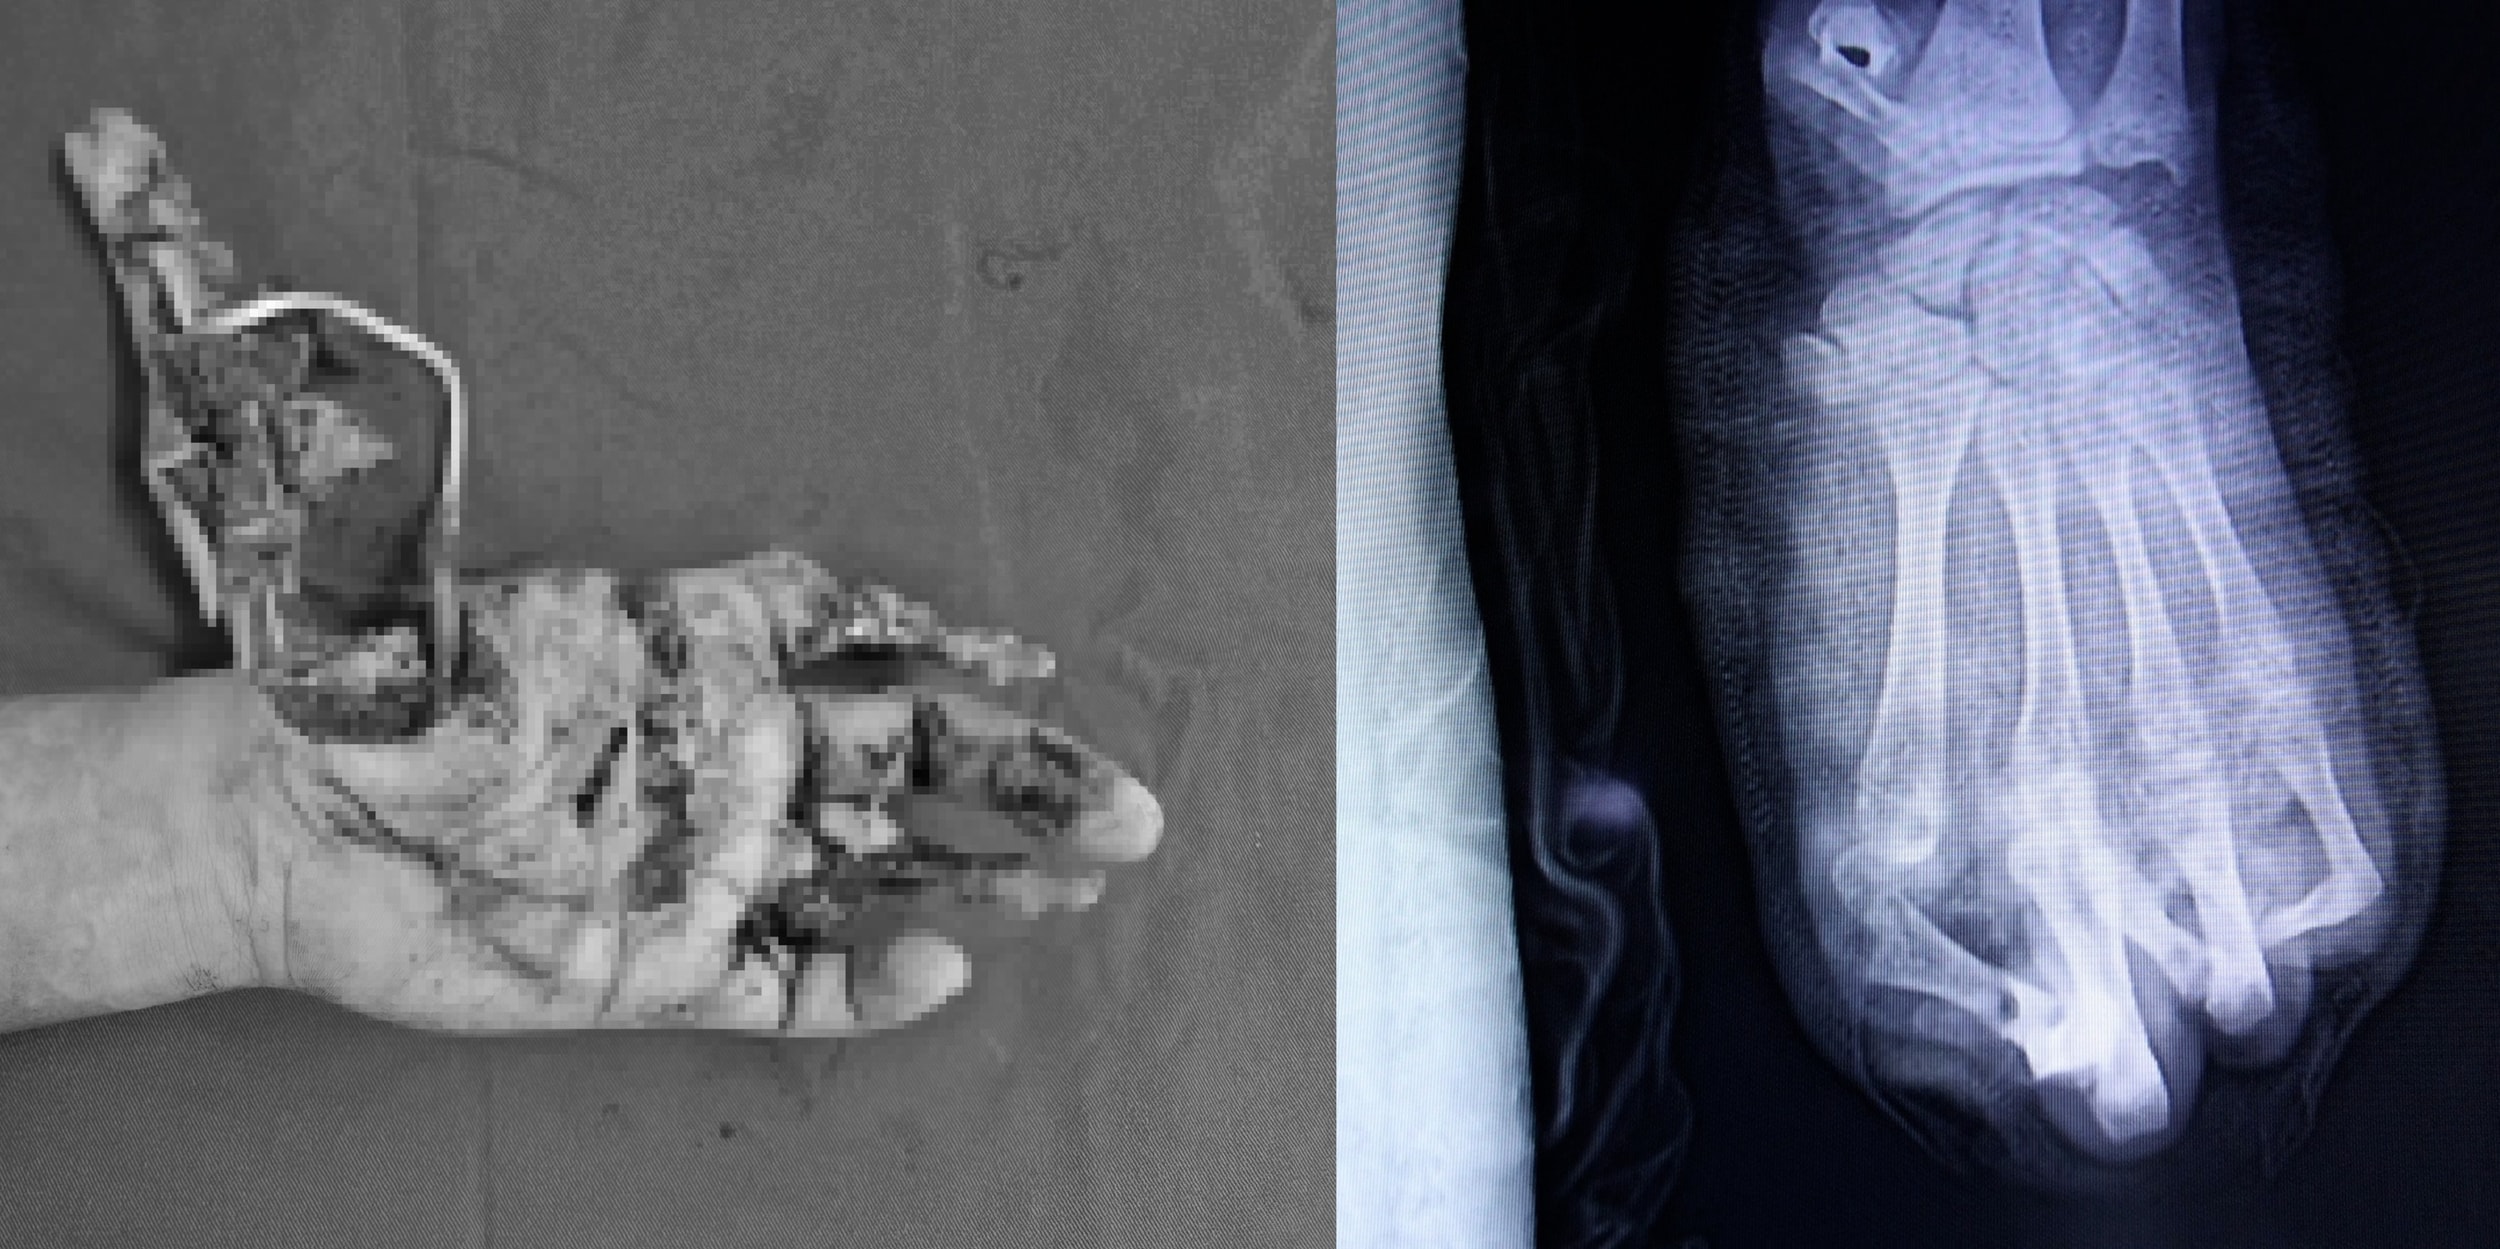

Tai nạn pháo nổ nghiêm trọng khiến thiếu niên 15 tuổi chỉ giữ được 2 ngón tay

(CLO) Dù được cấp cứu và phẫu thuật khẩn cấp, các bác sĩ chỉ có thể giữ lại 2/5 ngón tay, để lại nguy cơ mất chức năng bàn tay vĩnh viễn.